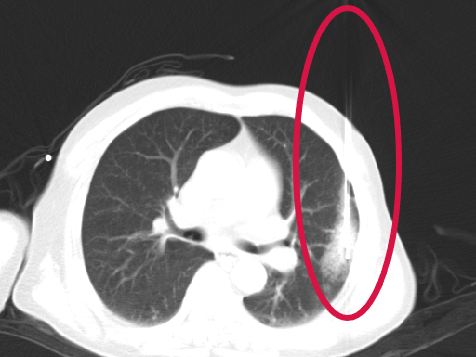

第二根消融針置入并開始消融

▲患者因體檢發(fā)現(xiàn)左肺上葉舌段結(jié)節(jié),考慮周圍型肺癌可能。因高齡、肺氣腫無法手術(shù),遂來院接受肺結(jié)節(jié)冷凍消融治療,術(shù)后病理為肺癌,定期隨訪提示腫瘤逐漸縮小。